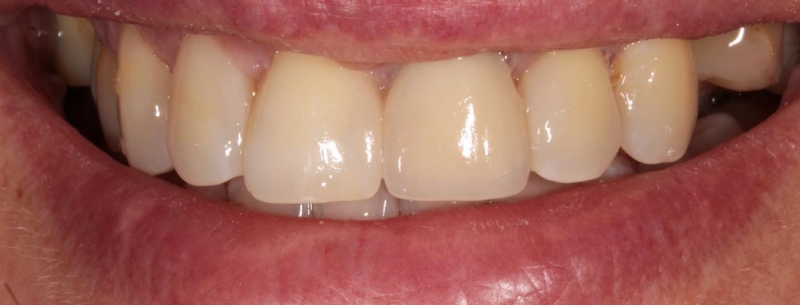

Профессиональная гигиена особенно важна при ортодонтическом лечении, ведь в повседневной жизни, дома, очень сложно поддерживать должный уровень гигиены полости рта! Даже если вы используете ирригатор и специальные ёршики! В нашей рубрике «до/после» вы видите то, что может быть с зубами при лечении брекетами, если не проводить своевременную чистку у врача-стоматолога. Марухно Дарья Александровна провела профессиональную чистку в несколько этапов, чтобы вернуть пациентке белизну ее собственных зубов! Брекет-система была поставлена не в нашей клинике, и почему пациентка не обратилась за профессиональной помощью раньше-вопрос) Но в данном случае, главное – итог! Кровоточивость после даже обычной чистки в такой клинической ситуации – естественный результат. Ведь обильный зубной налёт и зубной камень вызывают воспаление дёсен в виде гингивита, а порой даже пародонтита.

Доктор: Марухно Дарья Александровна